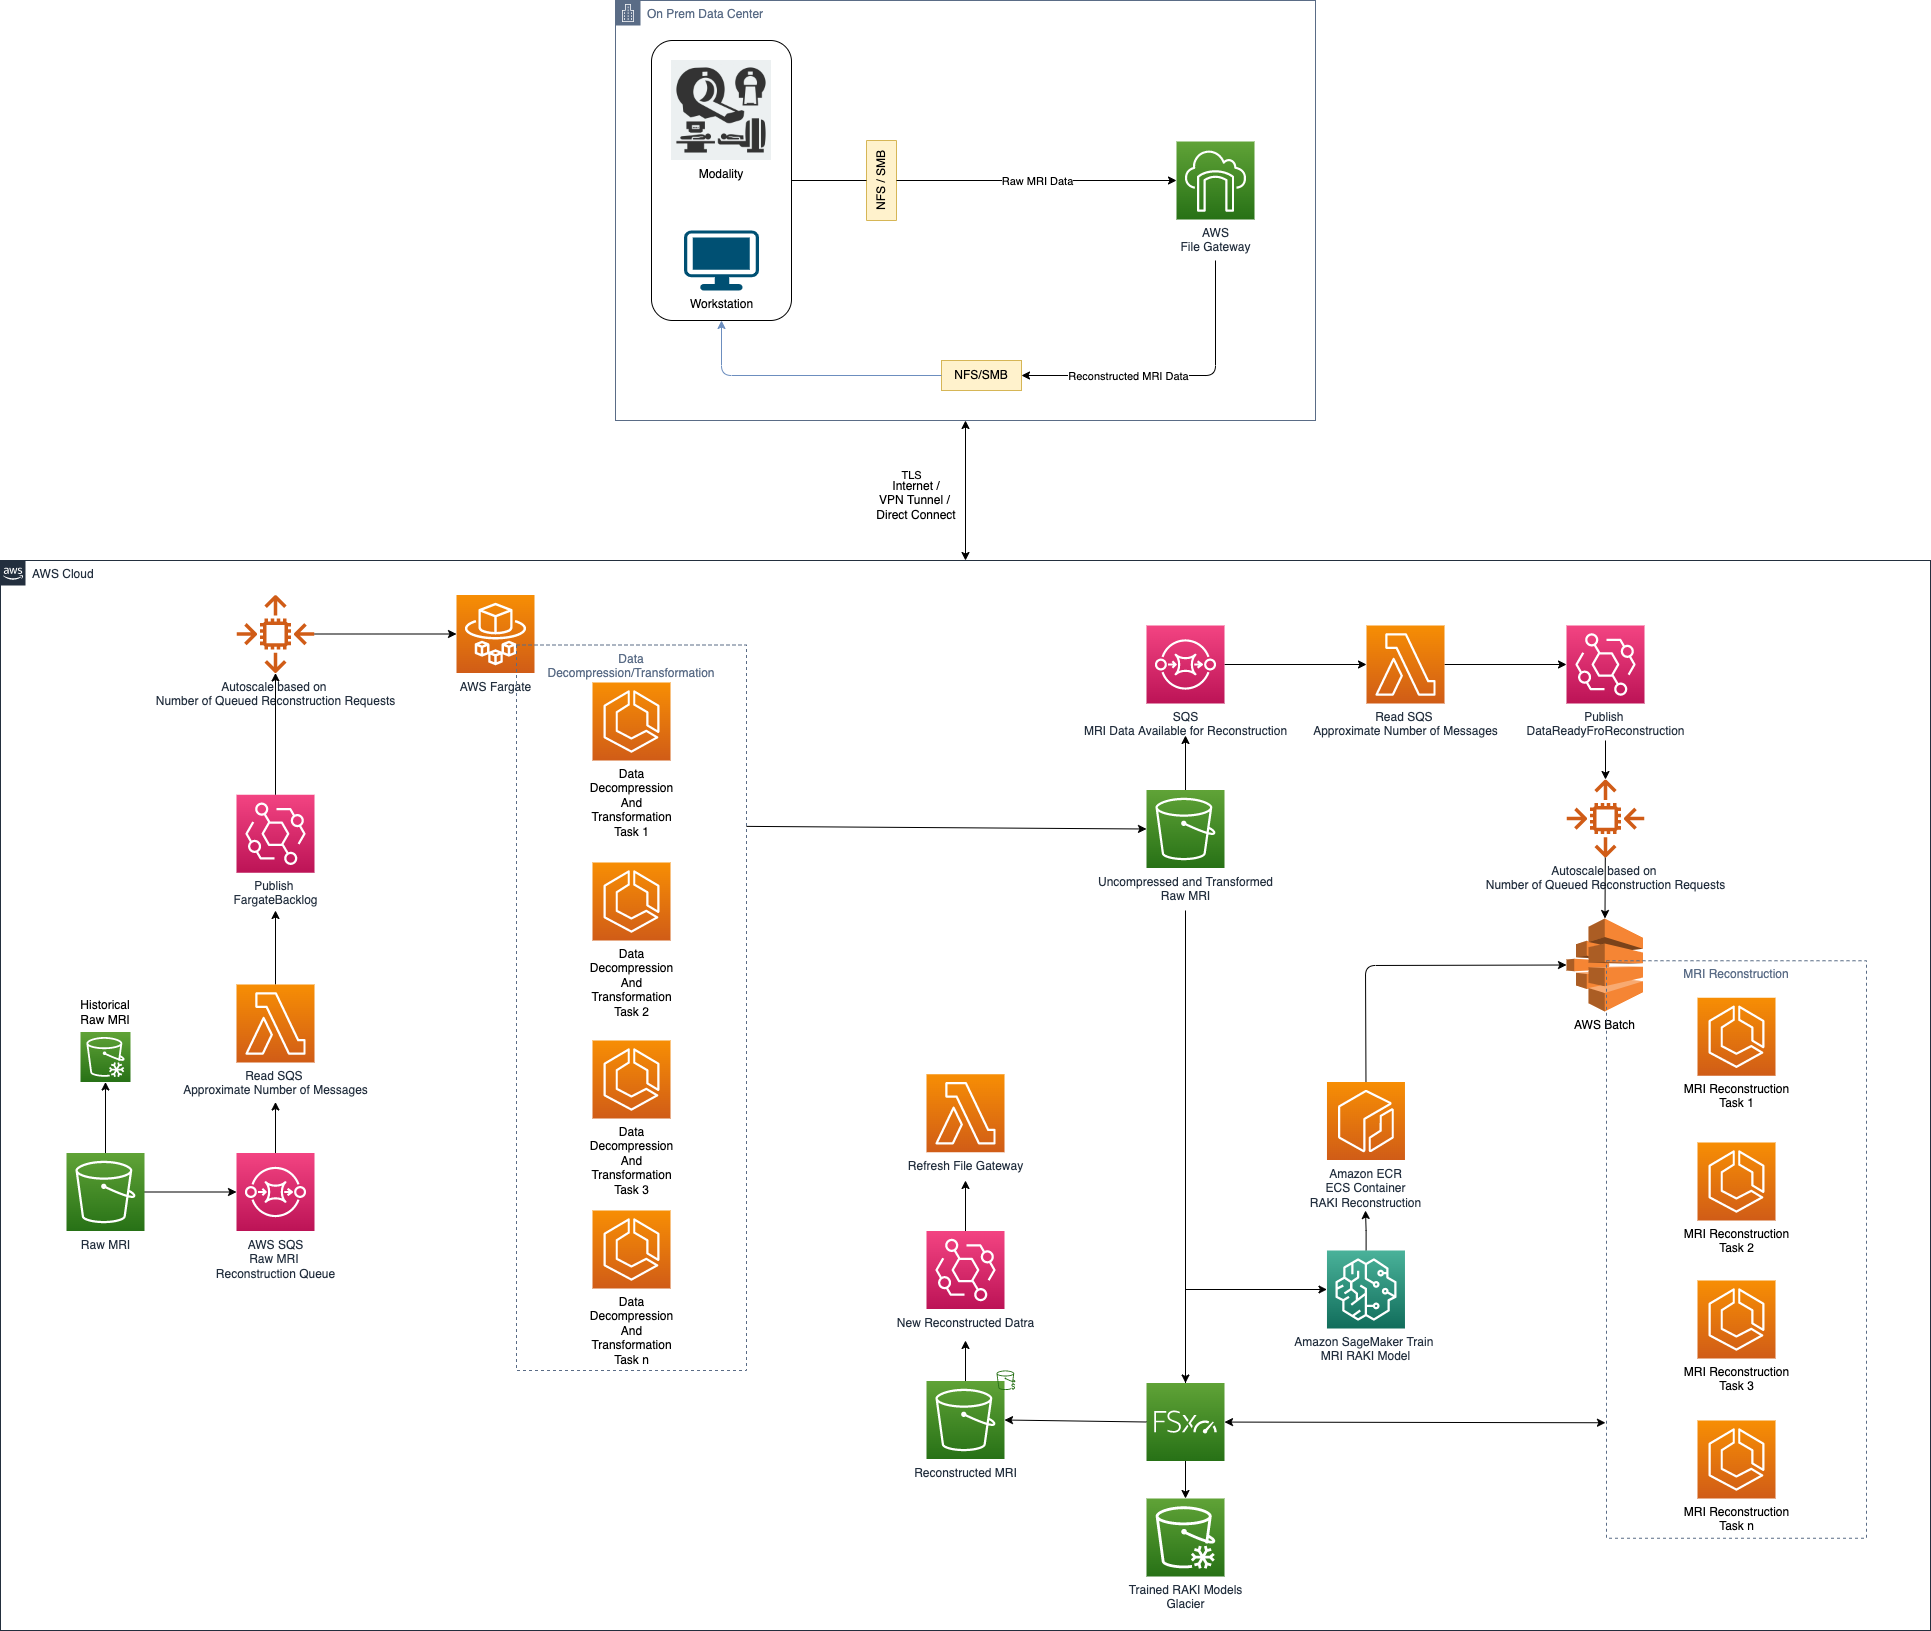

The overall architecture is shown in the following figure.

We applied the described architecture on MRI reconstruction tasks with datasets approximately 2.4 GB in size.

It took approximately 210 seconds to train 221 datasets, for a total of 514 GB of raw data on a single node equipped with a Nvidia Tesla V100-SXM2-16GB.

The reconstruction, after the RAKI network has been trained, took an average of 40 seconds on a single node equipped with a Nvidia Tesla V100-SXM2-16GB.

The image shows that good results can be obtained via reconstruction techniques such as RAKI. Moreover, adopting cloud technology can make these computation-heavy approaches available without the limitations found in on-premises solutions where storage and computational resources are always limited.

With tools such as Amazon SageMaker, Amazon FSx for Lustre, AWS Batch, Fargate, and Lambda, we can create a managed environment that is scalable, secure, cost-effective, and capable of performing complex tasks such as image reconstruction at scale.

In this post, we explored a possible solution for image reconstruction from raw modality data using a computationally intensive technique known as RAKI: a database free deep learning technique for fast image reconstruction.